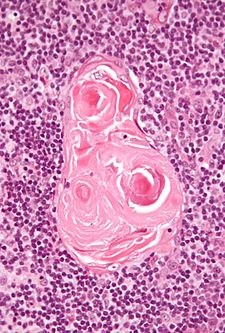

Features:[3]

- No germinal centres.

- Hassall's corpusle (thymic corpusle).

- Round eosinophilic thingy.

- Thought to arise from medullary epithelial cells (see cell types).[4]